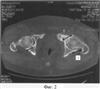

На фиг.2. представлен КТ срез на уровне нижней трети головки бедра.

Справа: 1-я стадия коксартроза с локализацией участков компрессии в заднем отделе сустава (1).

Слева: 3-я стадия коксартроза с кистевидной перестройкой с локализацией участков компрессии в заднем (1) и переднем отделах сустава (2).